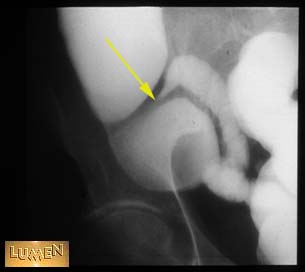

Question: Identify part of GI tract.

Ileocecal junction.